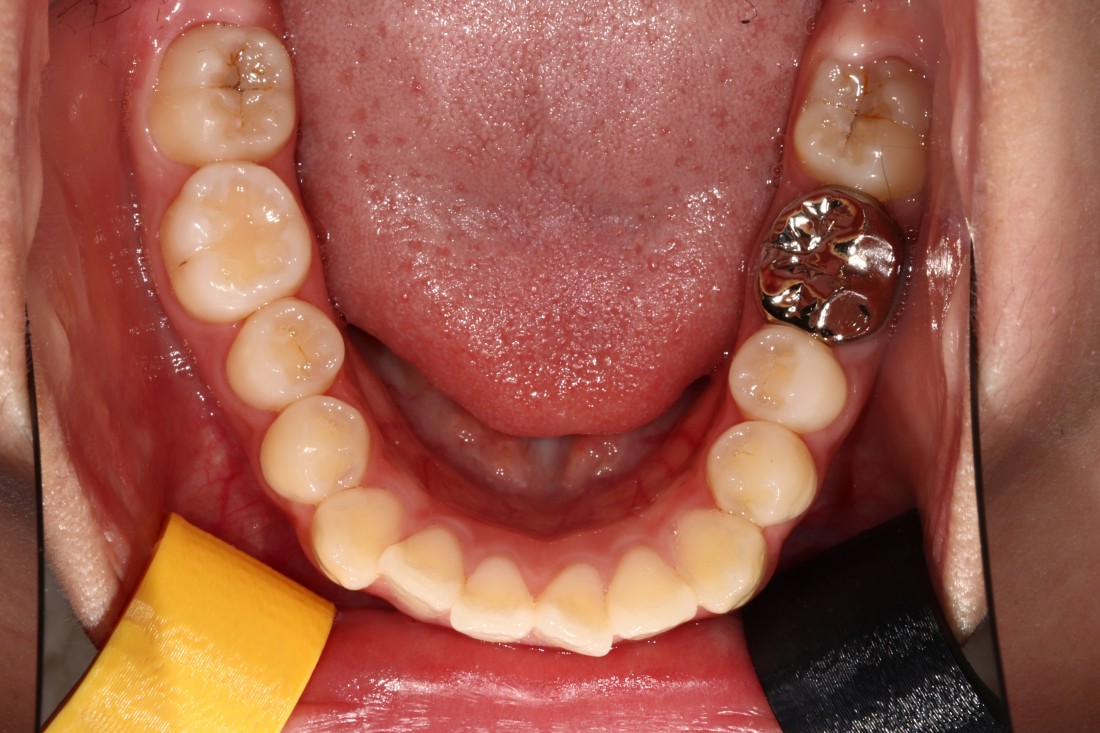

광주 성인 교정치과에서

충치치료와 교정진료를 동시에 받으신

성인 여성 환자분의 케이스입니다.

충치치료 전에는 은색 보철물이 있던 자리에

교정진료의 마무리와 동시에

치아색 보철물을 씌워서

치아교정 + 충치치료를 동시에 진행하였습니다.

광주 성인 치아교정의 경우

충치치료의 시기를 잘 판단하여

성공적인 진료를 완성할 수 있기 때문에

분과별 전문의가 협진하는

광주 성인 교정치과를 선택하시는 것이 좋습니다.